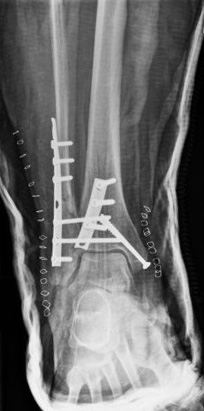

Visão da articulação de encaixe de uma fratura trimaleolar após a fixação. Nota: 2 parafusos na sindesmose também foram usados

Do acervo de B. Petrisor, MD; usado com permissão